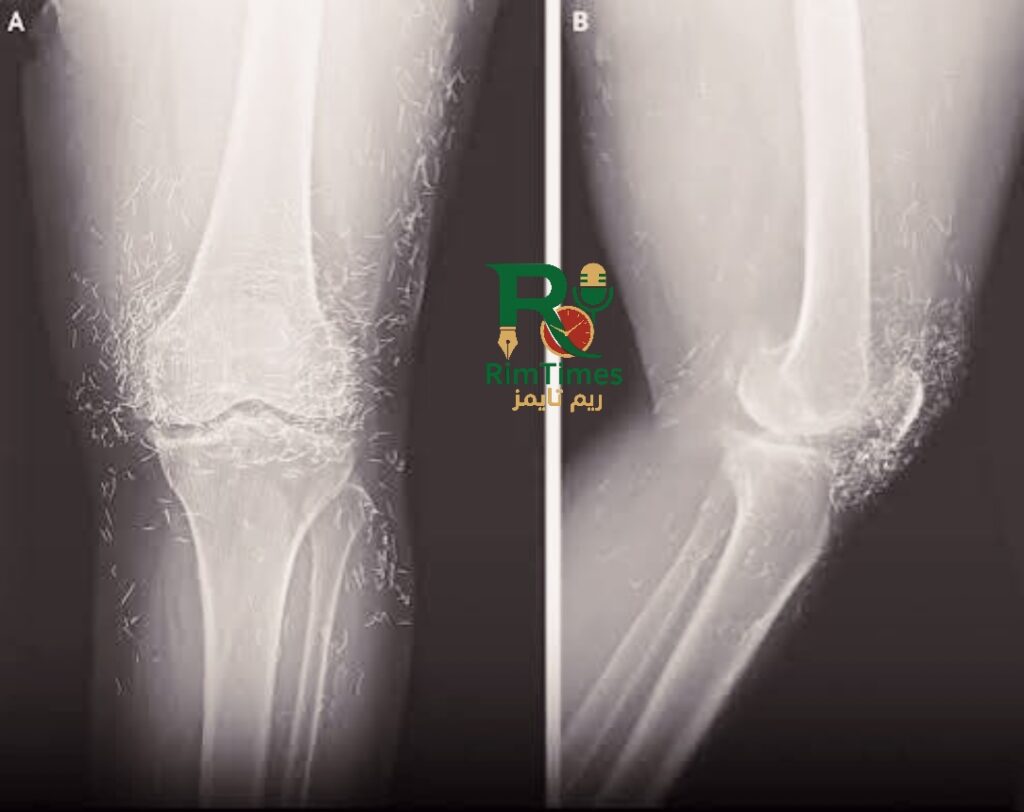

في واقعة نادرة ومثيرة للجدل الطبي، كشفت الأشعة السينية عن وجود مئات الخيوط الذهبية الدقيقة داخل مفاصل ركبتي امرأة كورية جنوبية تبلغ 65 عامًا، بعد أن توجهت إلى المستشفى تشكو من آلام حادة ومتكررة في الركبتين.

لكن الأشعة كشفت مفاجآت صادمة: مئات النقاط الصغيرة اللامعة حول الركبتين، إلى جانب زيادة سماكة العظام ونتوءات عظمية بجانب المفصل، وهي علامات على تفاقم التهاب المفاصل.